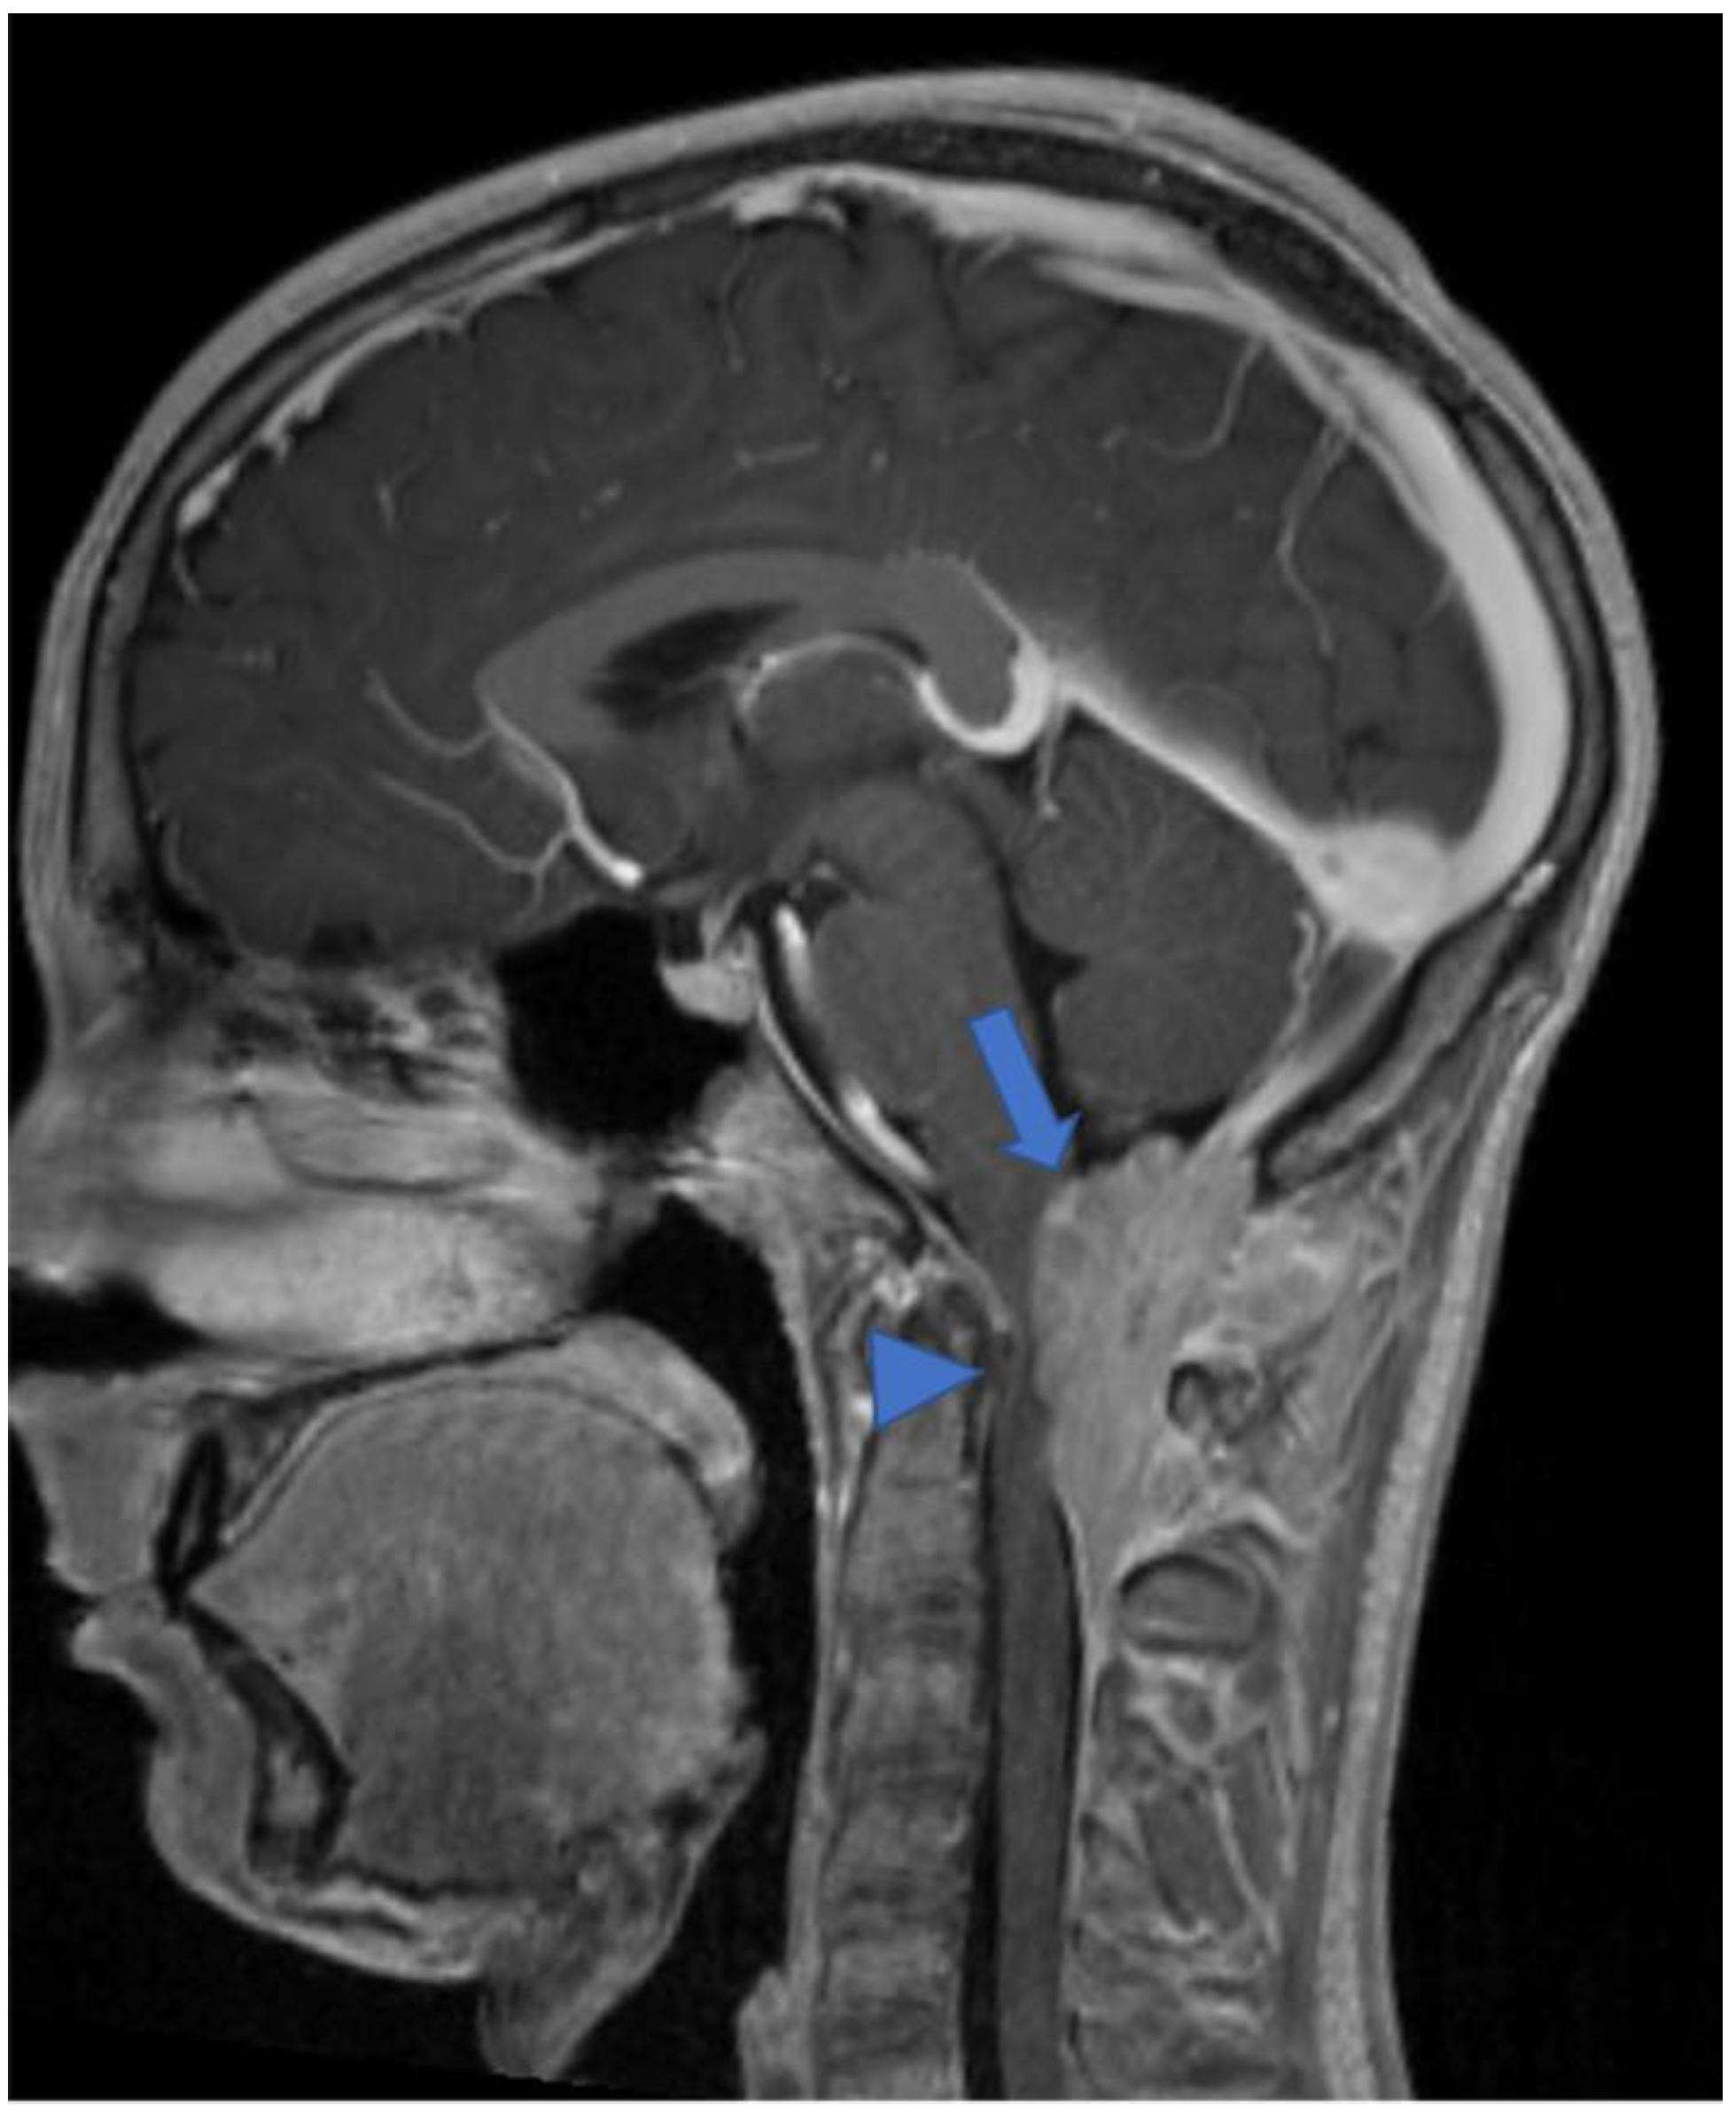

Figure 10.

Gadolinium-enhanced T1-weighted image. Craniocervical junction meningioma (arrow) characterized by dural base, well-defined margins, and intense and homogeneous enhancement. Compression and anterior dislocation of the bulb and cervical cord are evident (arrowhead).